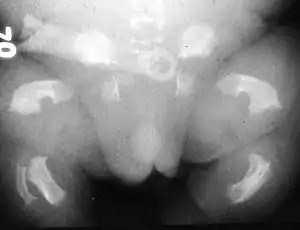

| Radiogram of a baby born with thanatophoric dwarfism | |

Infants with this condition have disproportionately short arms and legs with extra folds of skin. Other signs of the disorder include a narrow chest, small ribs, underdeveloped lungs, and an enlarged head with a large forehead and prominent, wide-spaced eyes. Thanatophoric dysplasia is a lethal skeletal dysplasia divided into two subtypes. Type I is characterized by extreme rhizomelia, bowed long bones, narrow thorax, a relatively large head, normal trunk length and absent cloverleaf skull. The spine shows platyspondyly, the cranium has a short base, and, frequently, the foramen magnum is decreased in size. The forehead is prominent, and hypertelorism and a saddle nose may be present. Hands and feet are normal, but fingers are short. Type II is characterized by short, straight long bones and cloverleaf skull.[1] It presents with typical telephone-handle shaped long bones and H-shaped vertebrae.

Infants with type 1 thanatophoric dysplasia also have curved thigh bones, flattened bones of the spine (platyspondyly) and shortened thoracic ribs. Note: Prenatal ultra-sound images of the ribs sometimes appear asymmetrical when in fact they are not. In certain cases, this has caused a misdiagnosis of Osteogenisis Imperfecta (OI) type II.